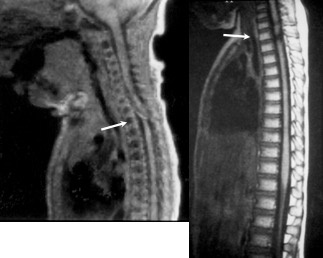

Il s’agit d’une lésion médullaire sans atteinte rachidienne liée à la compliance du rachis, donc une forme néonatale du SCIWORA. la présentation en siège est classiquement plus associée à un atteinte de la moelle thoracique, la présentation céphalique à une atteinte cervicale.

l’observation ci-dessous suggère malgré tout qu’une amélioration est possible après décompression chirurgicale.